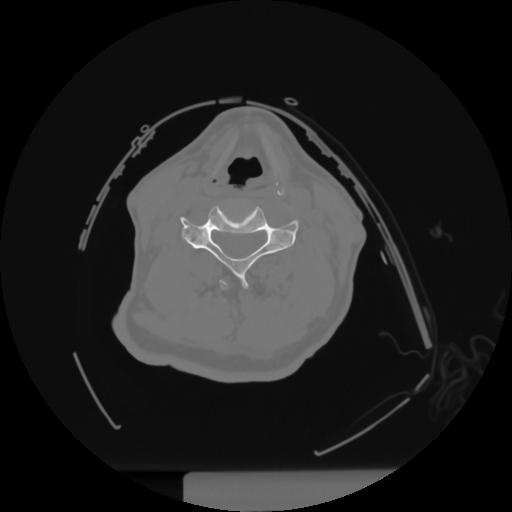

12 P.BLANDAS,,Vol,0.5,P.BLANDAS,,